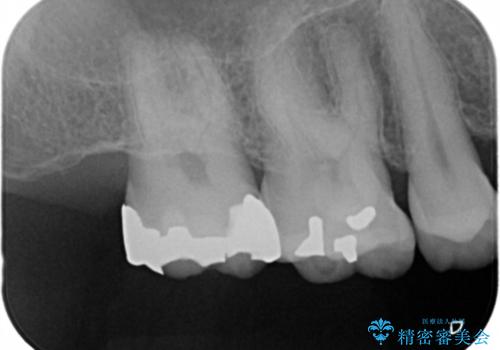

- 昔、治療された銀歯が気にな流ということを主訴で来院された患者様です。

銀歯を外し、虫歯治療を行い、セラミックインレーにて治療しました。

銀歯を除去し、虫歯をとって、セラミックインレーにて治療を行いました。